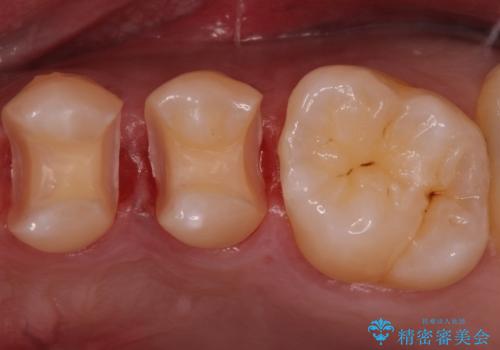

- 外から見える範囲の銀歯のやり替えをご希望で来院されました。

セラミックインレーでの治療となります。